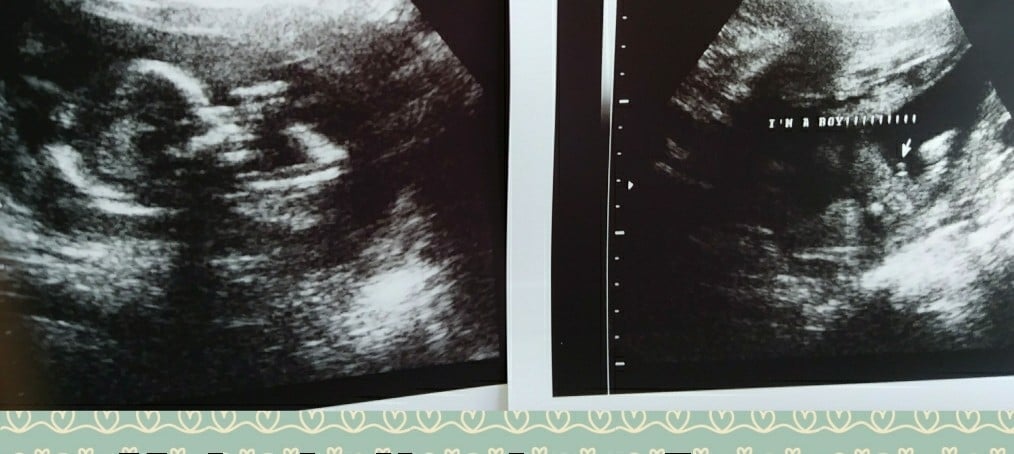

We had our first ultrasound at 10 weeks (I am 12 weeks now - due date at 11/19/18 - which is 3 days before my husband’s bday lol) I am a FTM, and thought this was so incredible. Seeing everything clearly definitely settled my nerves - the baby’s heart was fluttering at 154BPM and moving around like crazy! Our ultrasound tech showed us that she thinks it’s already a boy (my husband was THRILLED lol!) but we are waiting until W20 to confirm and before we start purchasing for the nursery. Now we can finally announce!

16+2 today and got to see my little man! Yup, found out today I’m having my third boy! Forever outnumbered!! He wouldn’t show us his face. He rolled every time we tried lol but he sure did give us a good hand shot and spread his legs WIDE open haha all junk today. Already a typical boy!